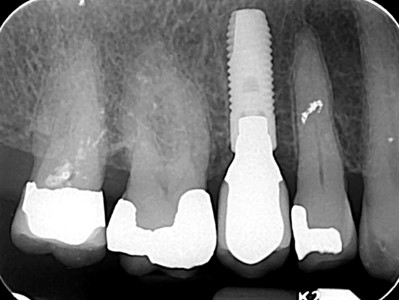

| Zdjęcie punktowe | 60 |

| Zdjęcie skrzydłowo-zgryzowe | 70 |

| Tomografia 5x5 (micro-CT) | 170 |